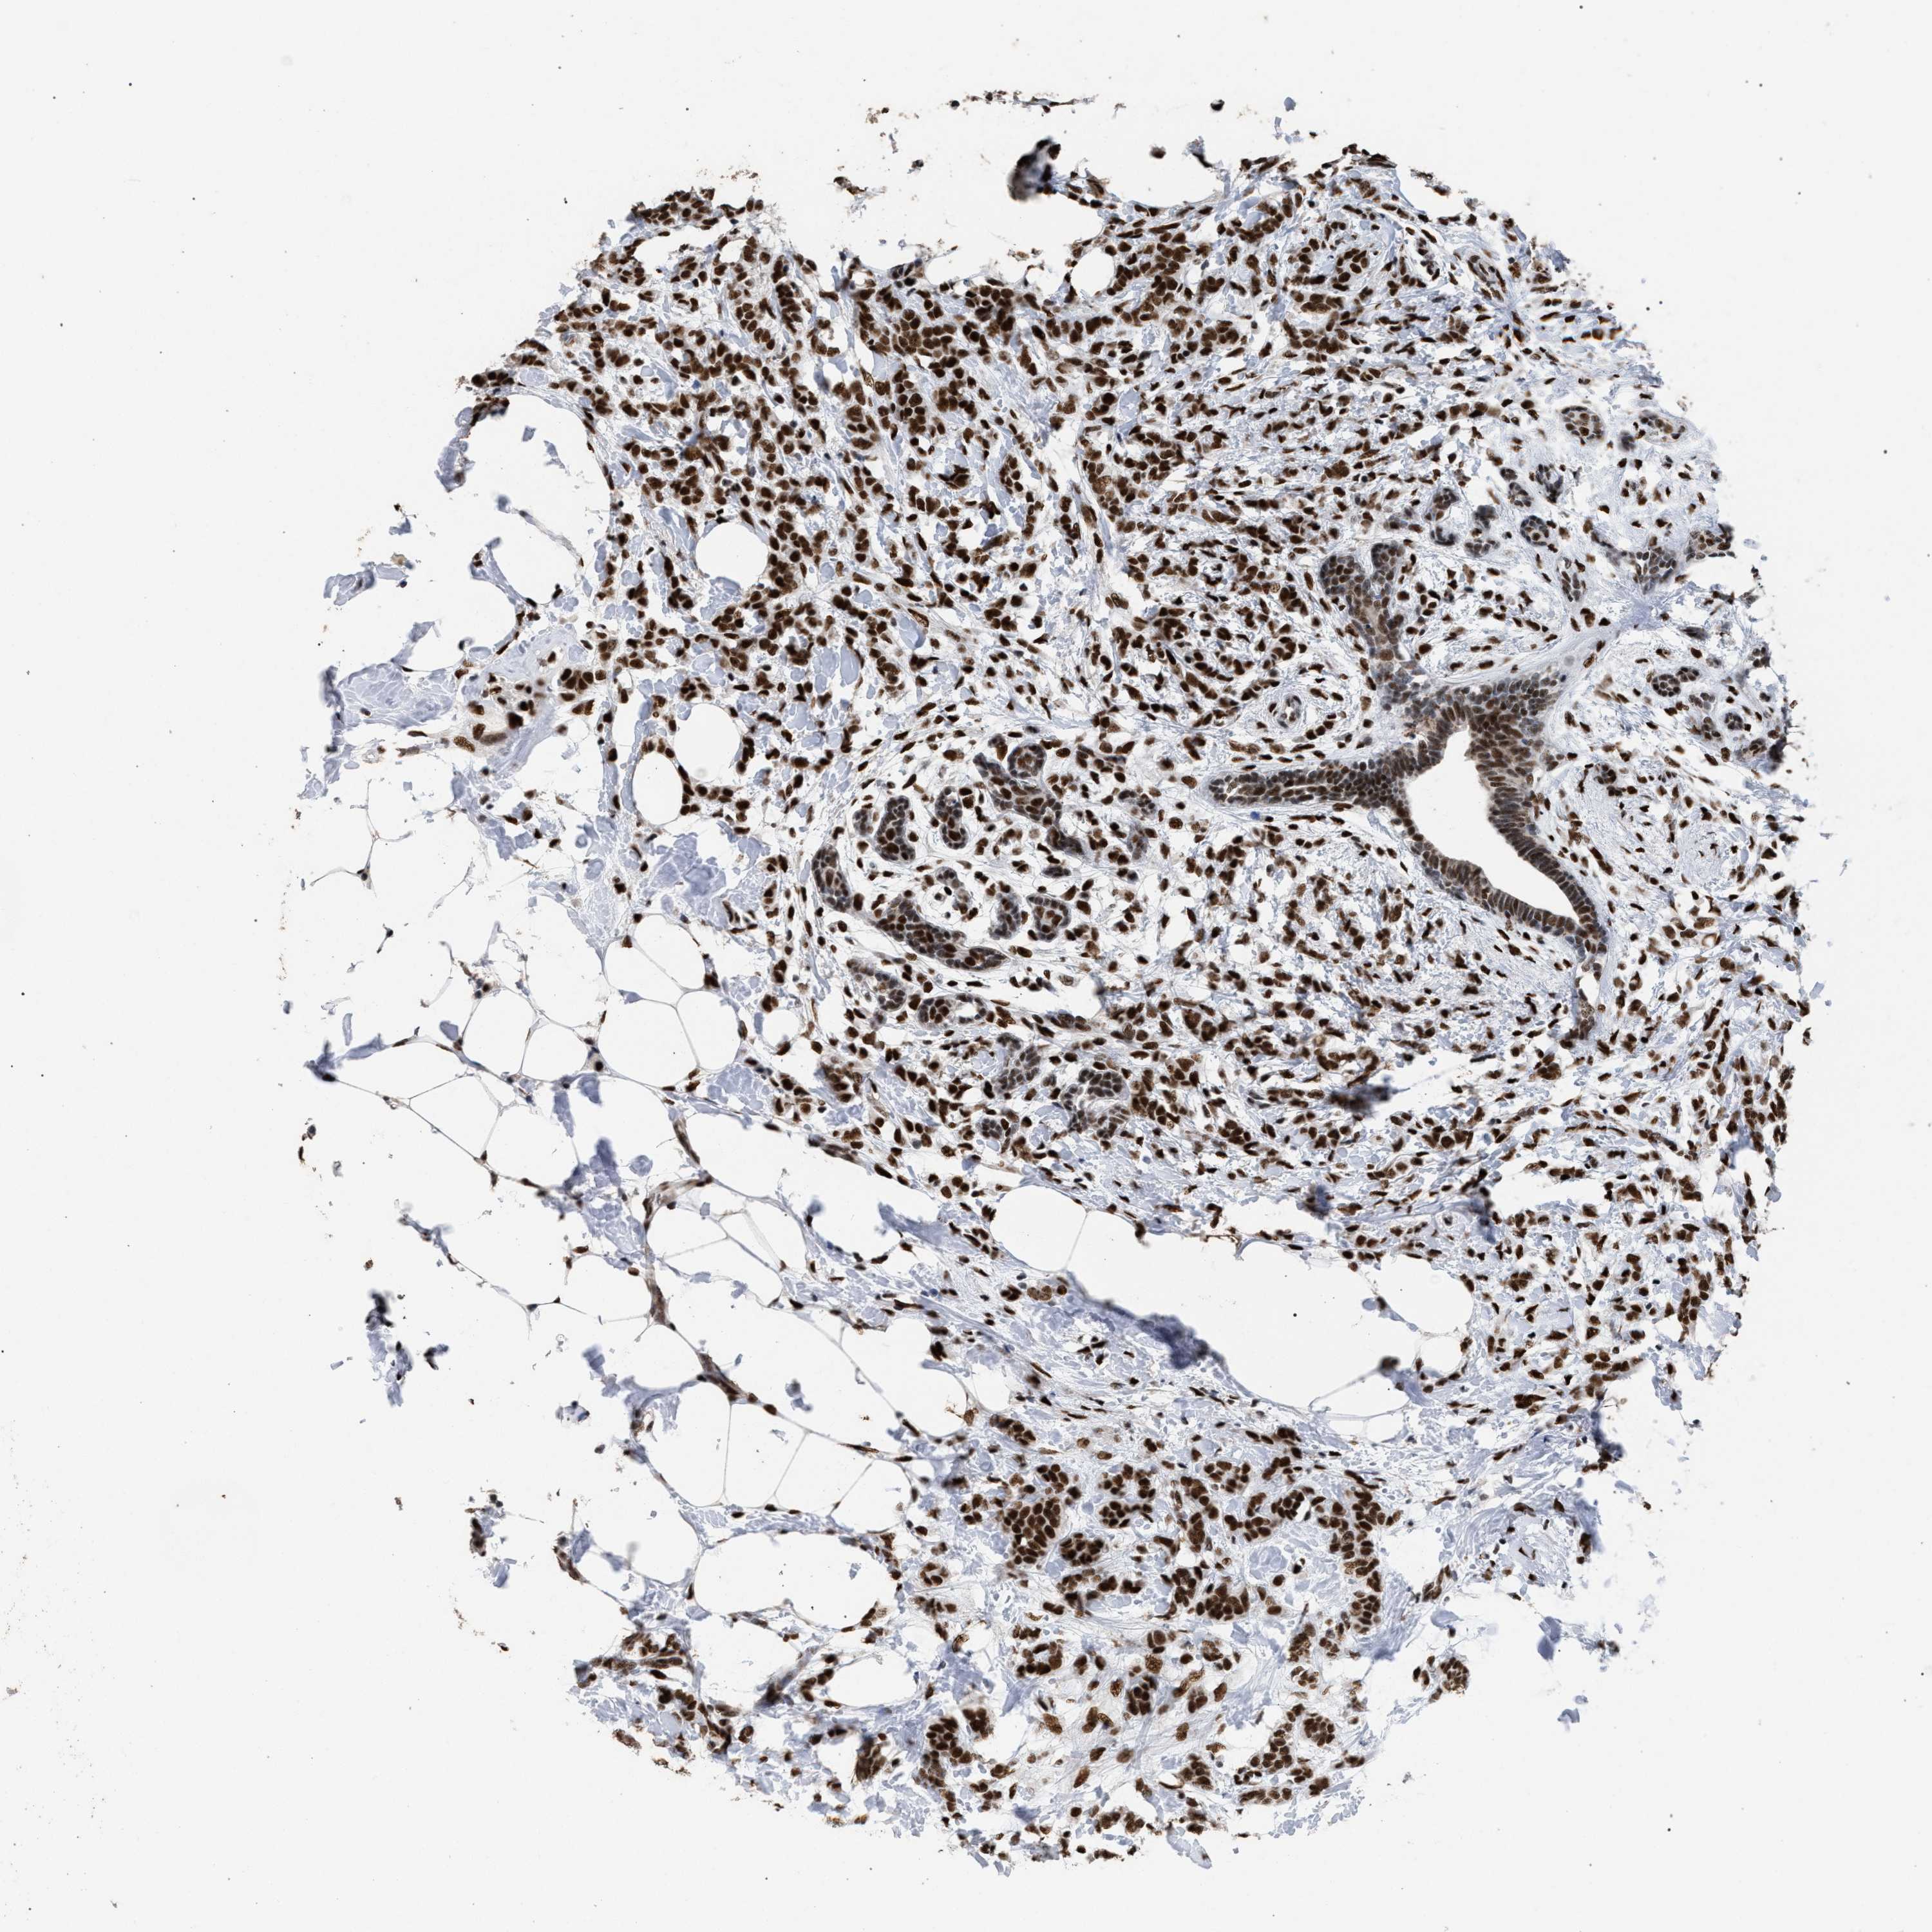

CANCER BREAST CANCER Show tissue menu

BRCA TCGA BRCA VALIDATION PROTEIN EXPRESSION

ANTIBODIES

AND

VALIDATION